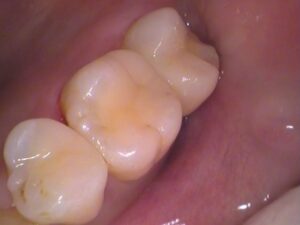

セラミックがセットされました

後日、出来上がったセラミックを装着します。

治療した箇所が分からないくらい綺麗に仕上がりました(^^)/

セラミックが入っていますが、色や形を歯に合わせているので、どこを治療したのか分かりませんね!

虫歯もなくなり、歯も綺麗に仕上がり、ケアしながら状態が長く保たれれば、歯の寿命が延び健康につながりますね(^-^)

こちらの患者さんは治療後、数日歯が凍みたものの落ち着き、今現在も気にならず食事も快適にできているとの事です。